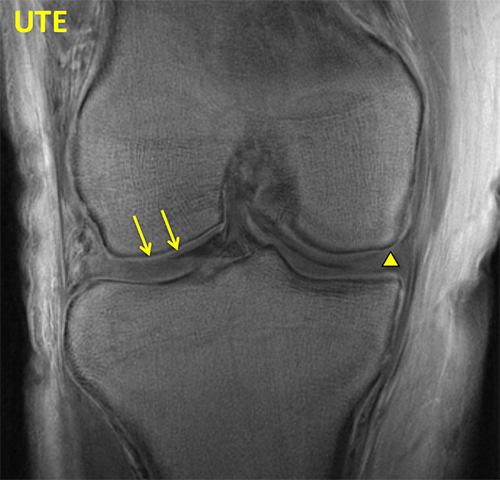

Knee UTE

UTE MRI reveals deep and calcified layers of articular cartilage (arrows) and menisci (triangle) with high signal intensity.